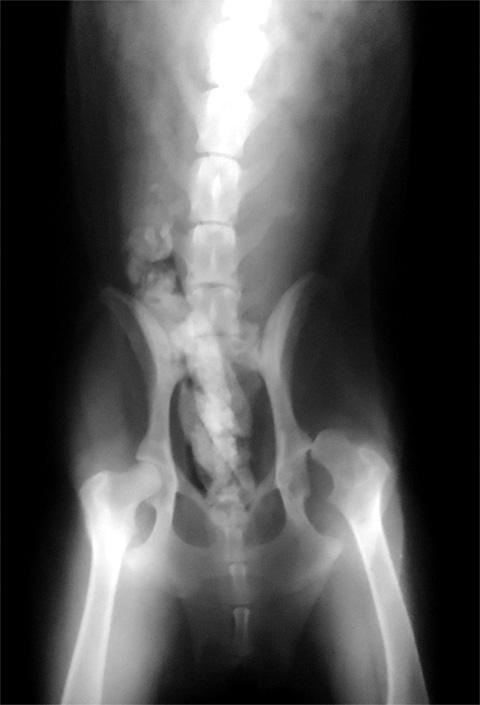

我花了一點時間拍了X光

請看一下目前的嚴重程度?

恩恩 另一腿非常的嚴重@_@!!

之後我讓他去拍X光,發現有很嚴重的髖關節

而且" 臼窩"還長出骨刺!!!! 讓我的狗生不如死

補充關於手術部分,狗兒會痛,是因為髖骨,和髖臼互相摩擦才會痛